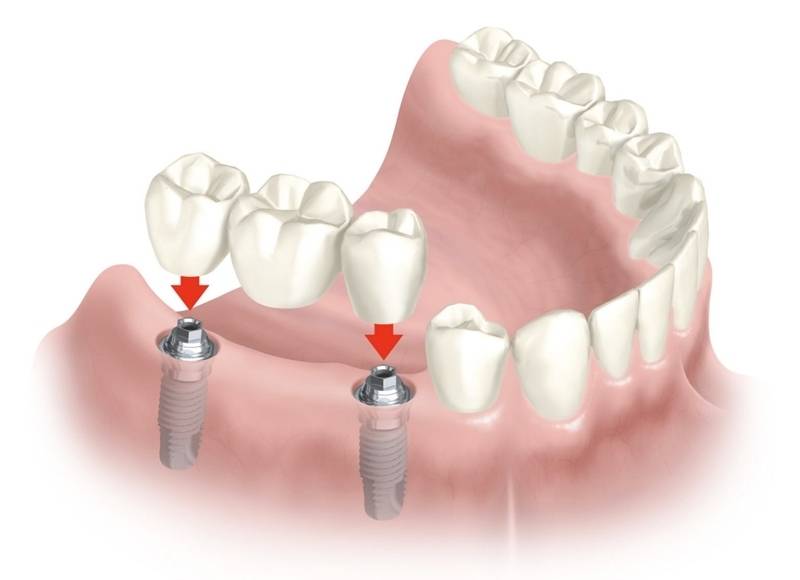

Implante dentário é formado por um cilindro (pino) de titânio, que é inserido dentro do osso, abaixo da gengiva. O tamanho do cilindro varia entre 3 e 6 mm de diâmetro. O titânio, metal biologicamente compatível que se integra perfeitamente ao osso, tem a peculiaridade de impedir qualquer tipo de rejeição óssea. Dessa forma, o implante dentário faz o papel da raiz do dente. Sobre os implantes é que são colocadas as próteses em metalocerâmica, que é o material mais semelhante ao dente natural.